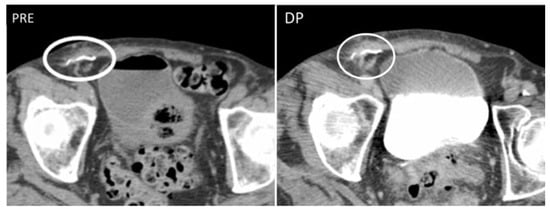

Figure 3. Granuloma occurring along a surgical mesh for an inguinal hernia repair. Axial CT on unenhanced (image on the left) and delayed phase at 10 min (image on the right) shows the formation of a nodular, fibrotic mass, with uptake contrast in delayed phases around a surgical mesh (circle).